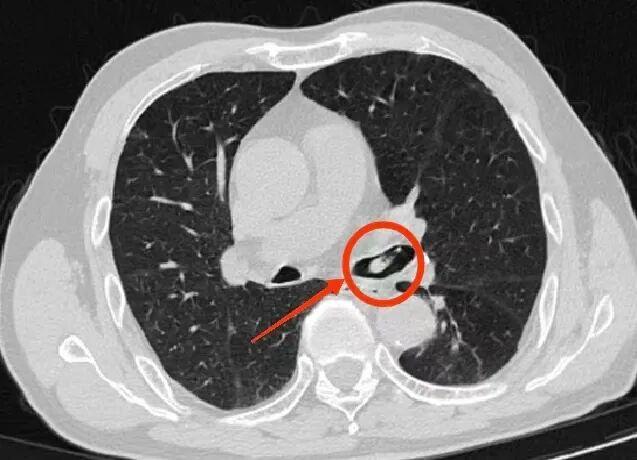

胸部CT显示,河虾已经下滑并卡在左主支气管管口。

呼吸与危重症医学科副主任李涛立即安排支气管镜检查,在纤细的镜管探入下,只见那只虾顽固地嵌在支气管管口,周围黏膜已微微红肿。李涛屏息凝神,用微型钳子轻柔夹取至咽喉部,这只“误入歧途”的河虾经杨先生口中咳出。